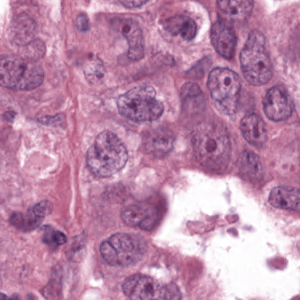

As an essential part of digital pathology, histopathology image analysis is playing increasingly important role in cancer diagnosis, which can provide direct and reliable evidence to diagnose the grade and type of cancer. This paper deals with nuclei segmentation, an important step in histopathological image analysis. The purpose of nuclei semgentation is not only counting the number of nuclei but also obtaining the detailed information of each nucleus. So unlike nuclei detection, here the outputs are the contour of each nucleus instead of only the position of their central points. Hence we can exactly extract each nucleus from the image and make it available for further analysis. For example, the features of the individual nucleus and the distribution of nuclei clusters can be used to grade and classify status of breast cancers [3, 4]. Because of appearance variation such as color, shape, and texture, nuclei segmentation from histopathological images could be very challenging, as illustrated in Fig.1, in which it is very challenging even for human to recognize and segment all nuclei within the images. Fig.1(a) and Fig.1(b) illustrate two histopathological images from different organs. Fig.1(c) and Fig.1(d) are two histopathological images from same organ but have different cancer grade.

II-B Data Preprocessing

H&E stain is the most widely used stain protocol in medical diagnosis. Typically, the nuclei of cells are stained to blue by Haematoxylin while cytoplasm is colored to pink by Eosin. But in practice, the color of H&E stained images could vary a lot due to variation in the H&E reagents, staining process, scanner and the specialist who performs the staining, as shown in Fig.1. A few H&E stain normalization methods[23, 24, 25] have been proposed to eliminate the negative interference caused by color variation. We tried two of them[23, 25] to normalize the raw H&E stained images. For our segmentation algorithm, we did not find any considerable difference between these two normalization methods. Particularly, the result shown in experiment section III is generated based on the images normalized by the method in [23]. Given a target image, this method is able to convert one image’s color into the target image’s color space based on sparse non-negative matrix factorization(NMF). We choose one best stained H&E image as the target and convert other images into its color space. According to the recommendation in [23], the hyper-parameter should be set between 0.01 and 0.1. In our experiment, is set to 0.1.

Figure 6 shows how our method segments the nuclei step by step. The color variety is well controlled by the color normalization procedure. The prediction result shows clear nuclear areas and nucleus boundaries. In the final segmentation result and ground truth image, each nucleus is represented by a different color.